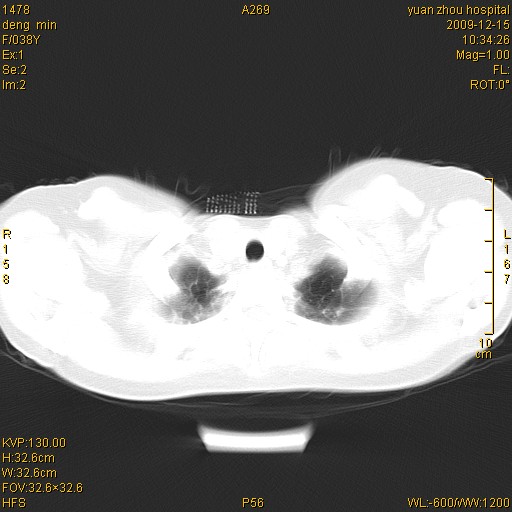

标题: CT23919:F38Y 咳嗽月余 [打印本页]

标题: CT23919:F38Y 咳嗽月余

右肺中下叶、左肺上叶舌段及左肺下叶支气管扩张合并感染。